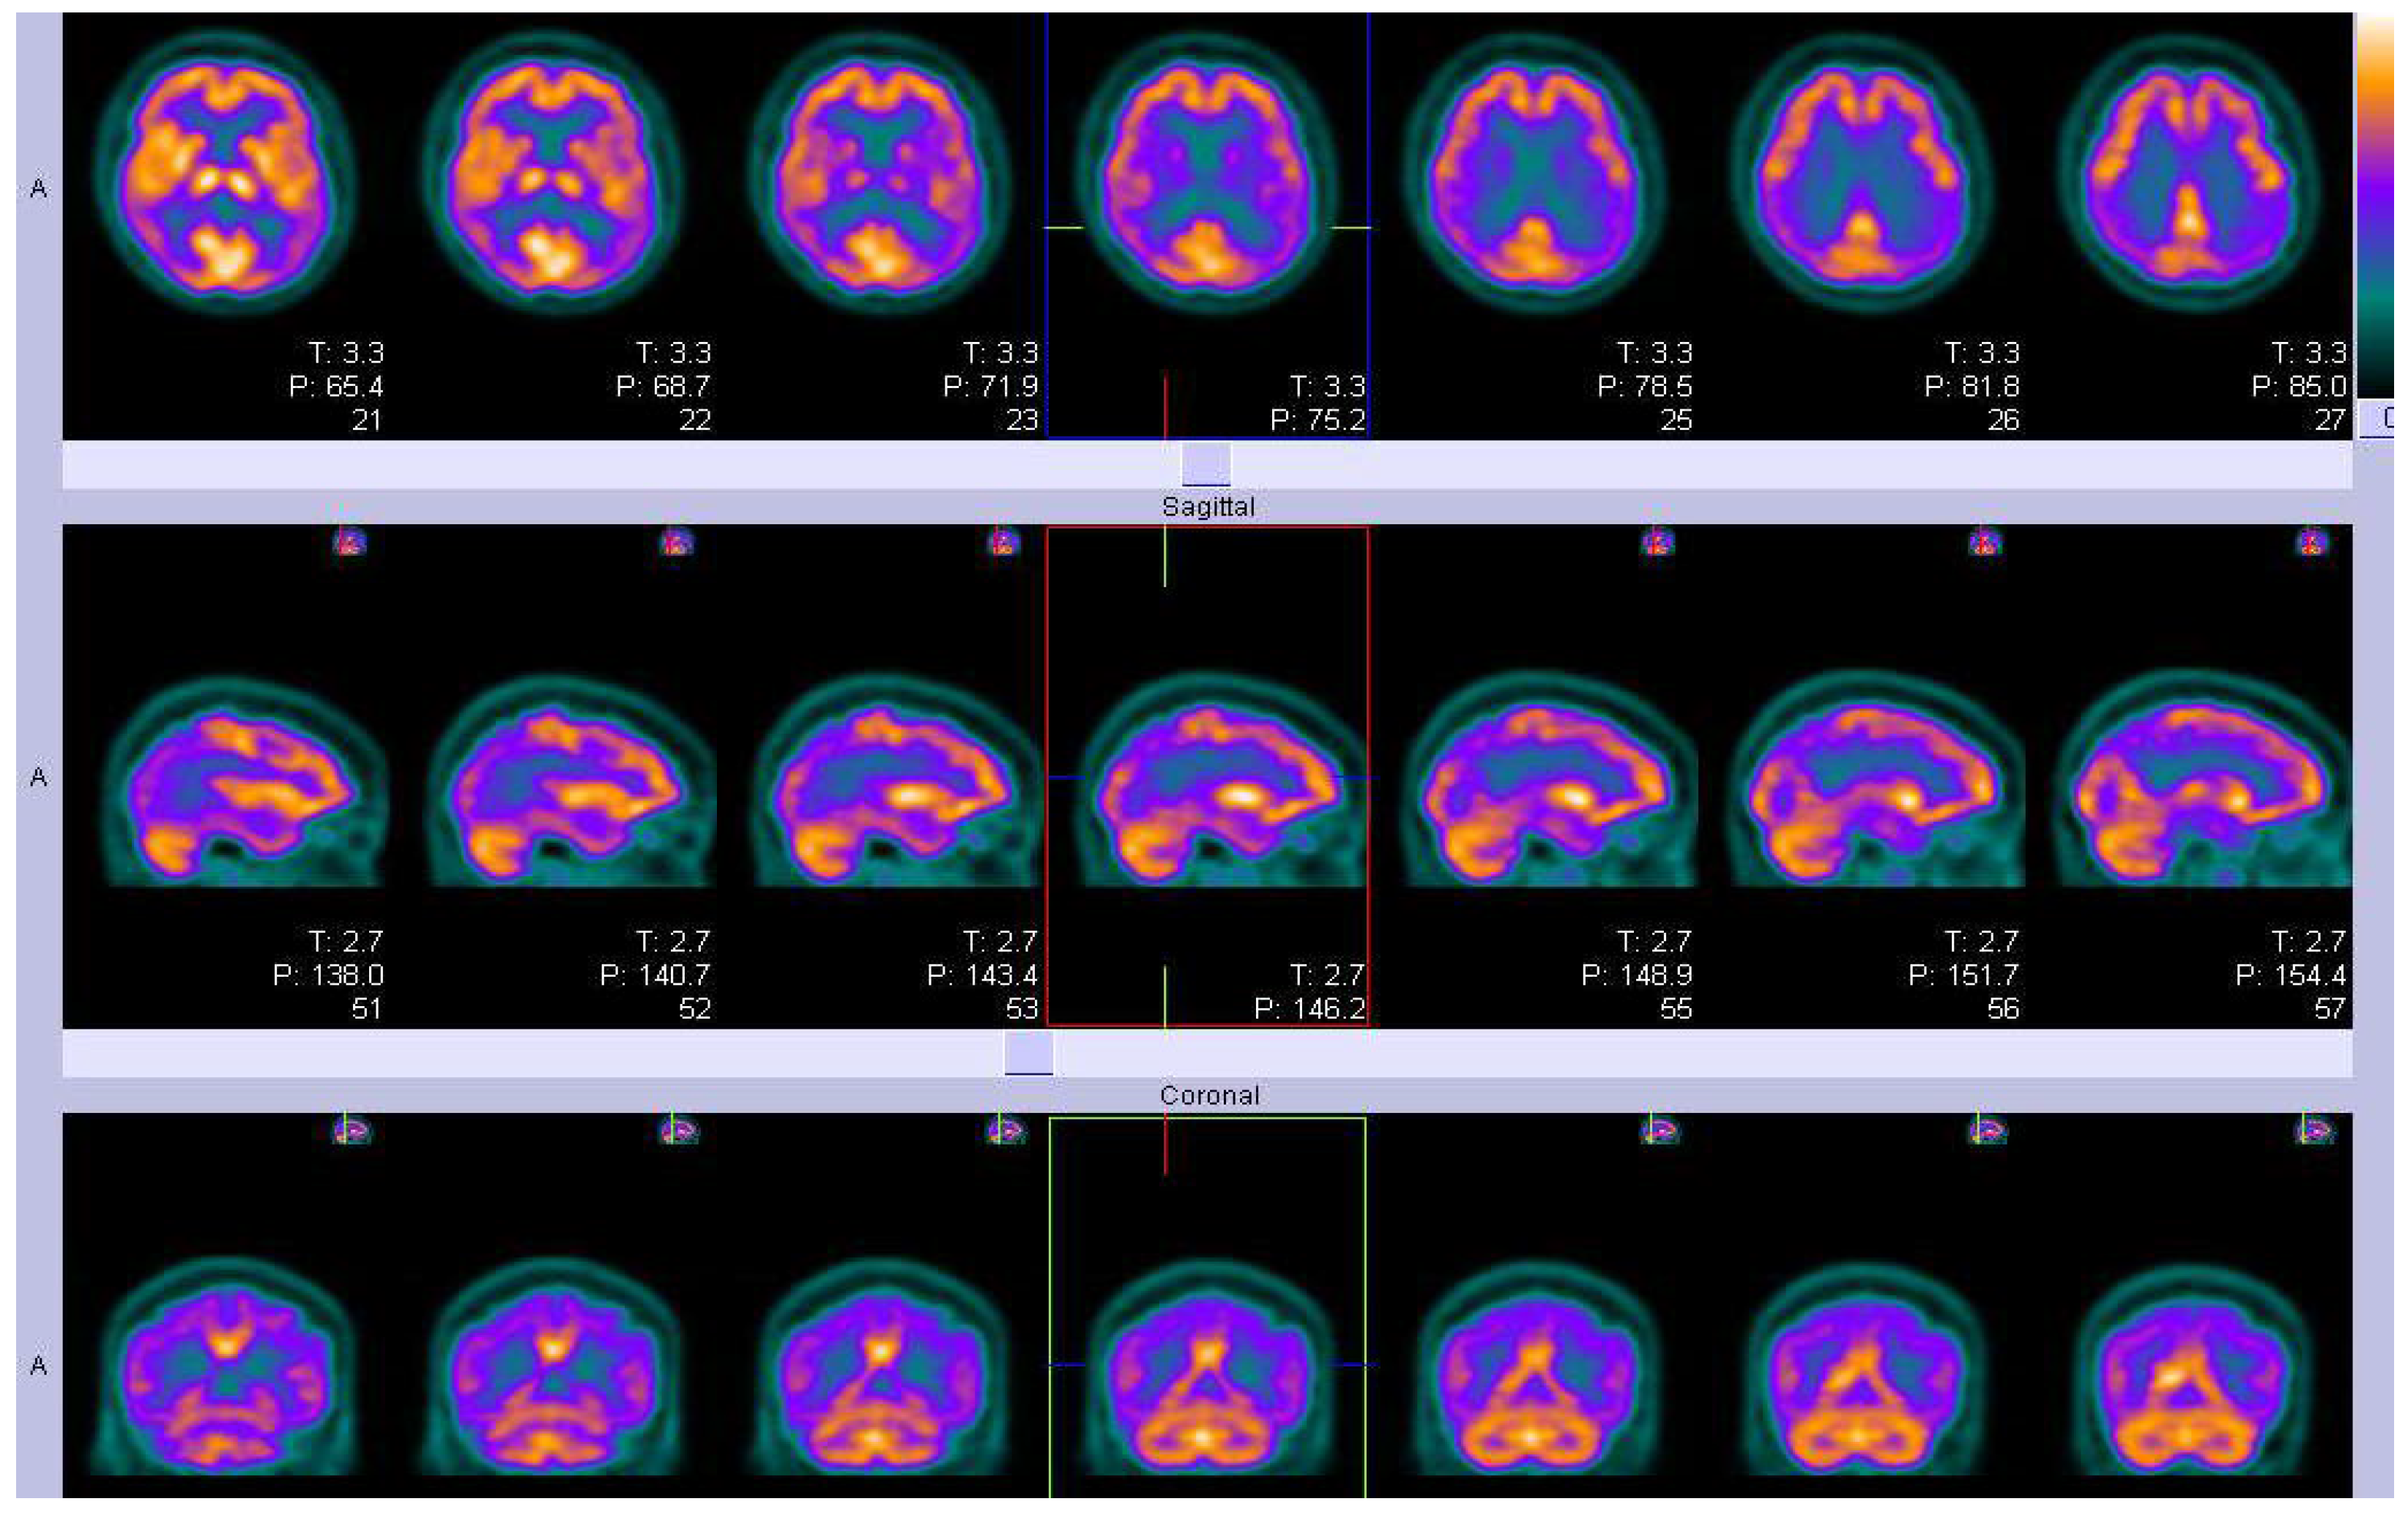

Figure 2.

An example of FDG-PET imaging in a participant from an Alzheimer’s disease clinical trial who met research criteria for probable AD, showing temporo-parietal hypo-metabolism(violet diagonal band) and normal areas of metabolism(golden). T is the thickness (2.2 mm) and P is the position relative to the isocentre of the field of view(FoV).(Courtesy—Alison D. Murray, University of Aberdeen).